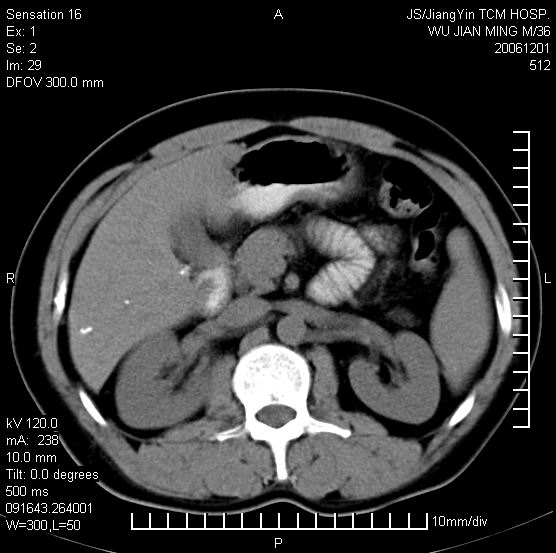

以下是引用dyqct在2006-12-1 21:17:00的发言:[br]左心缘旁及后肋膈窦区见巨大椭圆形混杂密度肿块,周围见大小不等斑片状钙化,内部无强化,周围包膜轻度强化,心脏明显受压变形,即明显占位效应,肿块广基与心包、膈相连。肝、脾内、肝门见多数小结节状钙化影。[br]考虑:1、左心缘旁及后肋膈窦区慢性包裹性胸膜炎(结核性);[br] 2、肝、脾及肝门淋巴结核已钙化。[br]

以下是引用zrs在2006-12-2 17:28:00的发言:[br]肺内、肝脾内虽有钙化,但不支持结核性胸胸膜炎包裹,而支持寄生虫感染![br][br]

以下是引用zyx168在2006-12-2 10:10:00的发言:[br][br]肝脾肺内多发钙化灶